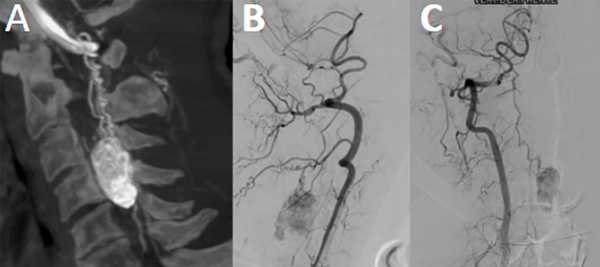

Paciente masculino de 67 años sin antecedentes de relevancia que consultó por cuadro de cervicalgia de 5 meses de evolución. Progresó con disminución de la fuerza de miembros superiores a predominio izquierdo de carácter distal sumado a hipoestesia de dedos de ambas manos. Se realizó RM que evidenció una lesión intradural-extramedular de carácter nodular en topografía C3-C4 que comprime y desplaza la médula a izquierda, con realce homogéneo con contraste. La angiografía digital permitió identificar aferencias por arterias radiculo-medulares posterolaterales bilaterales con drenaje venoso ascendente y signos de hipertensión venosa posterior. No se realizó embolización preoperatoria.

Fig 2. Caso 1. Angiografía cervical espinal evidenciando “blush” tumoral con aferencia primaria de arteria espinal posterior (A, B y C).

Fig 8. Caso 3. Angiografía espinal torácica: evidenciando lesión hiper vacularizada con aferencia primaria de ramo radiculomedular lateral izquierdo, de arteria intercostal. Con drenaje venoso descendente por venas perimedulares anteriores y posteriores (A y B).